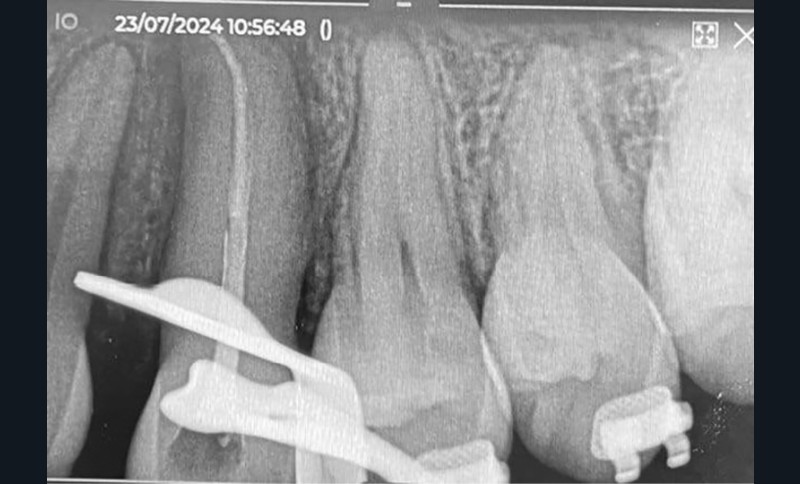

Des radiographies rétro-alvéolaires de contrôle sont effectuées au cours du traitement, il est recommandé de ne pas entreprendre de mouvement orthodontique pendant 4 mois à l’arcade maxillaire.

L’auto-transplantation de la 23 sur l’arcade, qui était en position très défavorable, et malgré un apex fermé présente de bons résultats. La radiographie rétro-alvéolaire (fig. 19) montre une intégrité de l’état radiculaire de la dent auto-transplantée. Un suivi régulier reste cependant nécessaire.